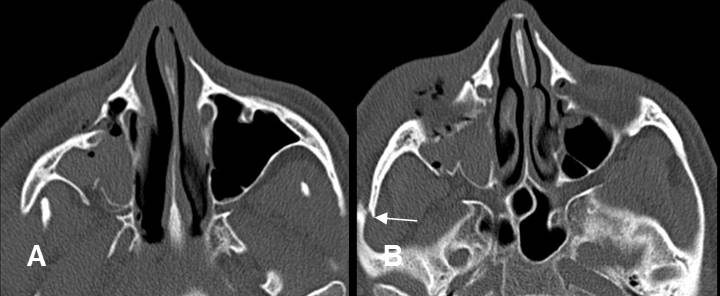

Fig 214. Fractura del arco cigomático.

A y B: TAC axial. Fracturas del arco cigomático. Lineal en A y deprimida en B.

En ambos casos hay otras fracturas asociadas de los antros maxilares.